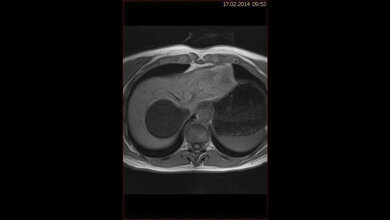

Um frühzeitig mit präventiven und therapeutischen Maßnahmen intervenieren zu können, muss die Fettleber rechtzeitig erkannt werden. Hierfür sind die Ultraschalluntersuchung der Leber und die Bestimmung der Leberwerte zwar geeignet, sie können die Fettleber aber meist nur in einem fortgeschrittenen Stadium diagnostizieren. Aufwändigere Untersuchungen wie die Kernspinspektroskopie sind hierfür zwar aussagekräftiger, sie sind aber wegen der relativ hohen Kosten im klinischen Alltag nicht auf breiter Ebene einsatzfähig. Daher arbeiten Wissenschaftler weltweit an einfachen und genauen Methoden, die für die Diagnose einer Fettleber besser geeignet sind. Unter verschiedenen Indizes, die dafür entwickelt wurden, hat sich der ‚Fatty Liver Index‘ (FLI) bestehend aus den Parametern Alter, Body-Mass-Index, Taillenumfang und den im Nüchternzustand im Blut gemessenen Werten für Triglyzeride (TG) und Gamma-Glutamyltranspeptidase (GGT), als recht effektiv erwiesen.